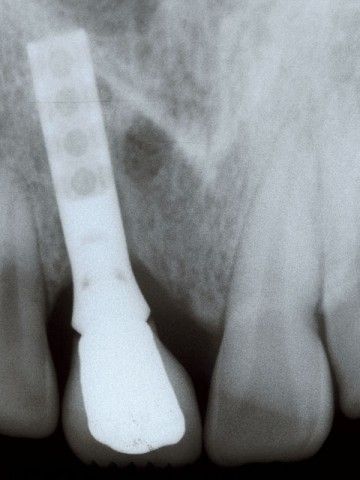

Το περιστατικό στις φωτογραφίες είναι του 1998 και αφορά αποκατάσταση απώλειας δοντιών και οστού στην πρόσθια άνω περιοχή από τροχαίο ατύχημα:

Στη φωτογραφία η αποκατάσταση ενός άνω κεντρικού τομέα το 1997 με αισθητικά υλικά και εμφυτευματική στήριξη.